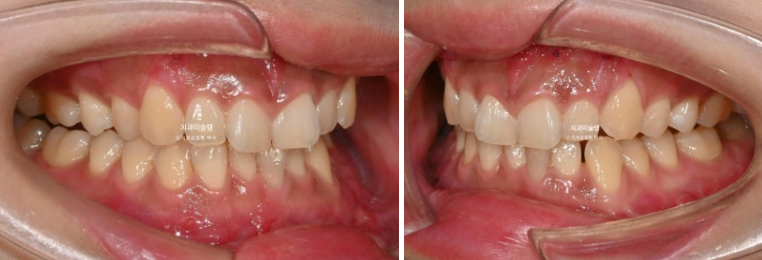

선수술 후 한달간의 회복기를 거쳐 25년 1월 본원에 내원했을 때의 교합 상태입니다.

25.01

앞니 두 개는 나비치아 돌출이며

어금니 교합이 떠있습니다.

앞니에 배열이 삐뚤합니다.